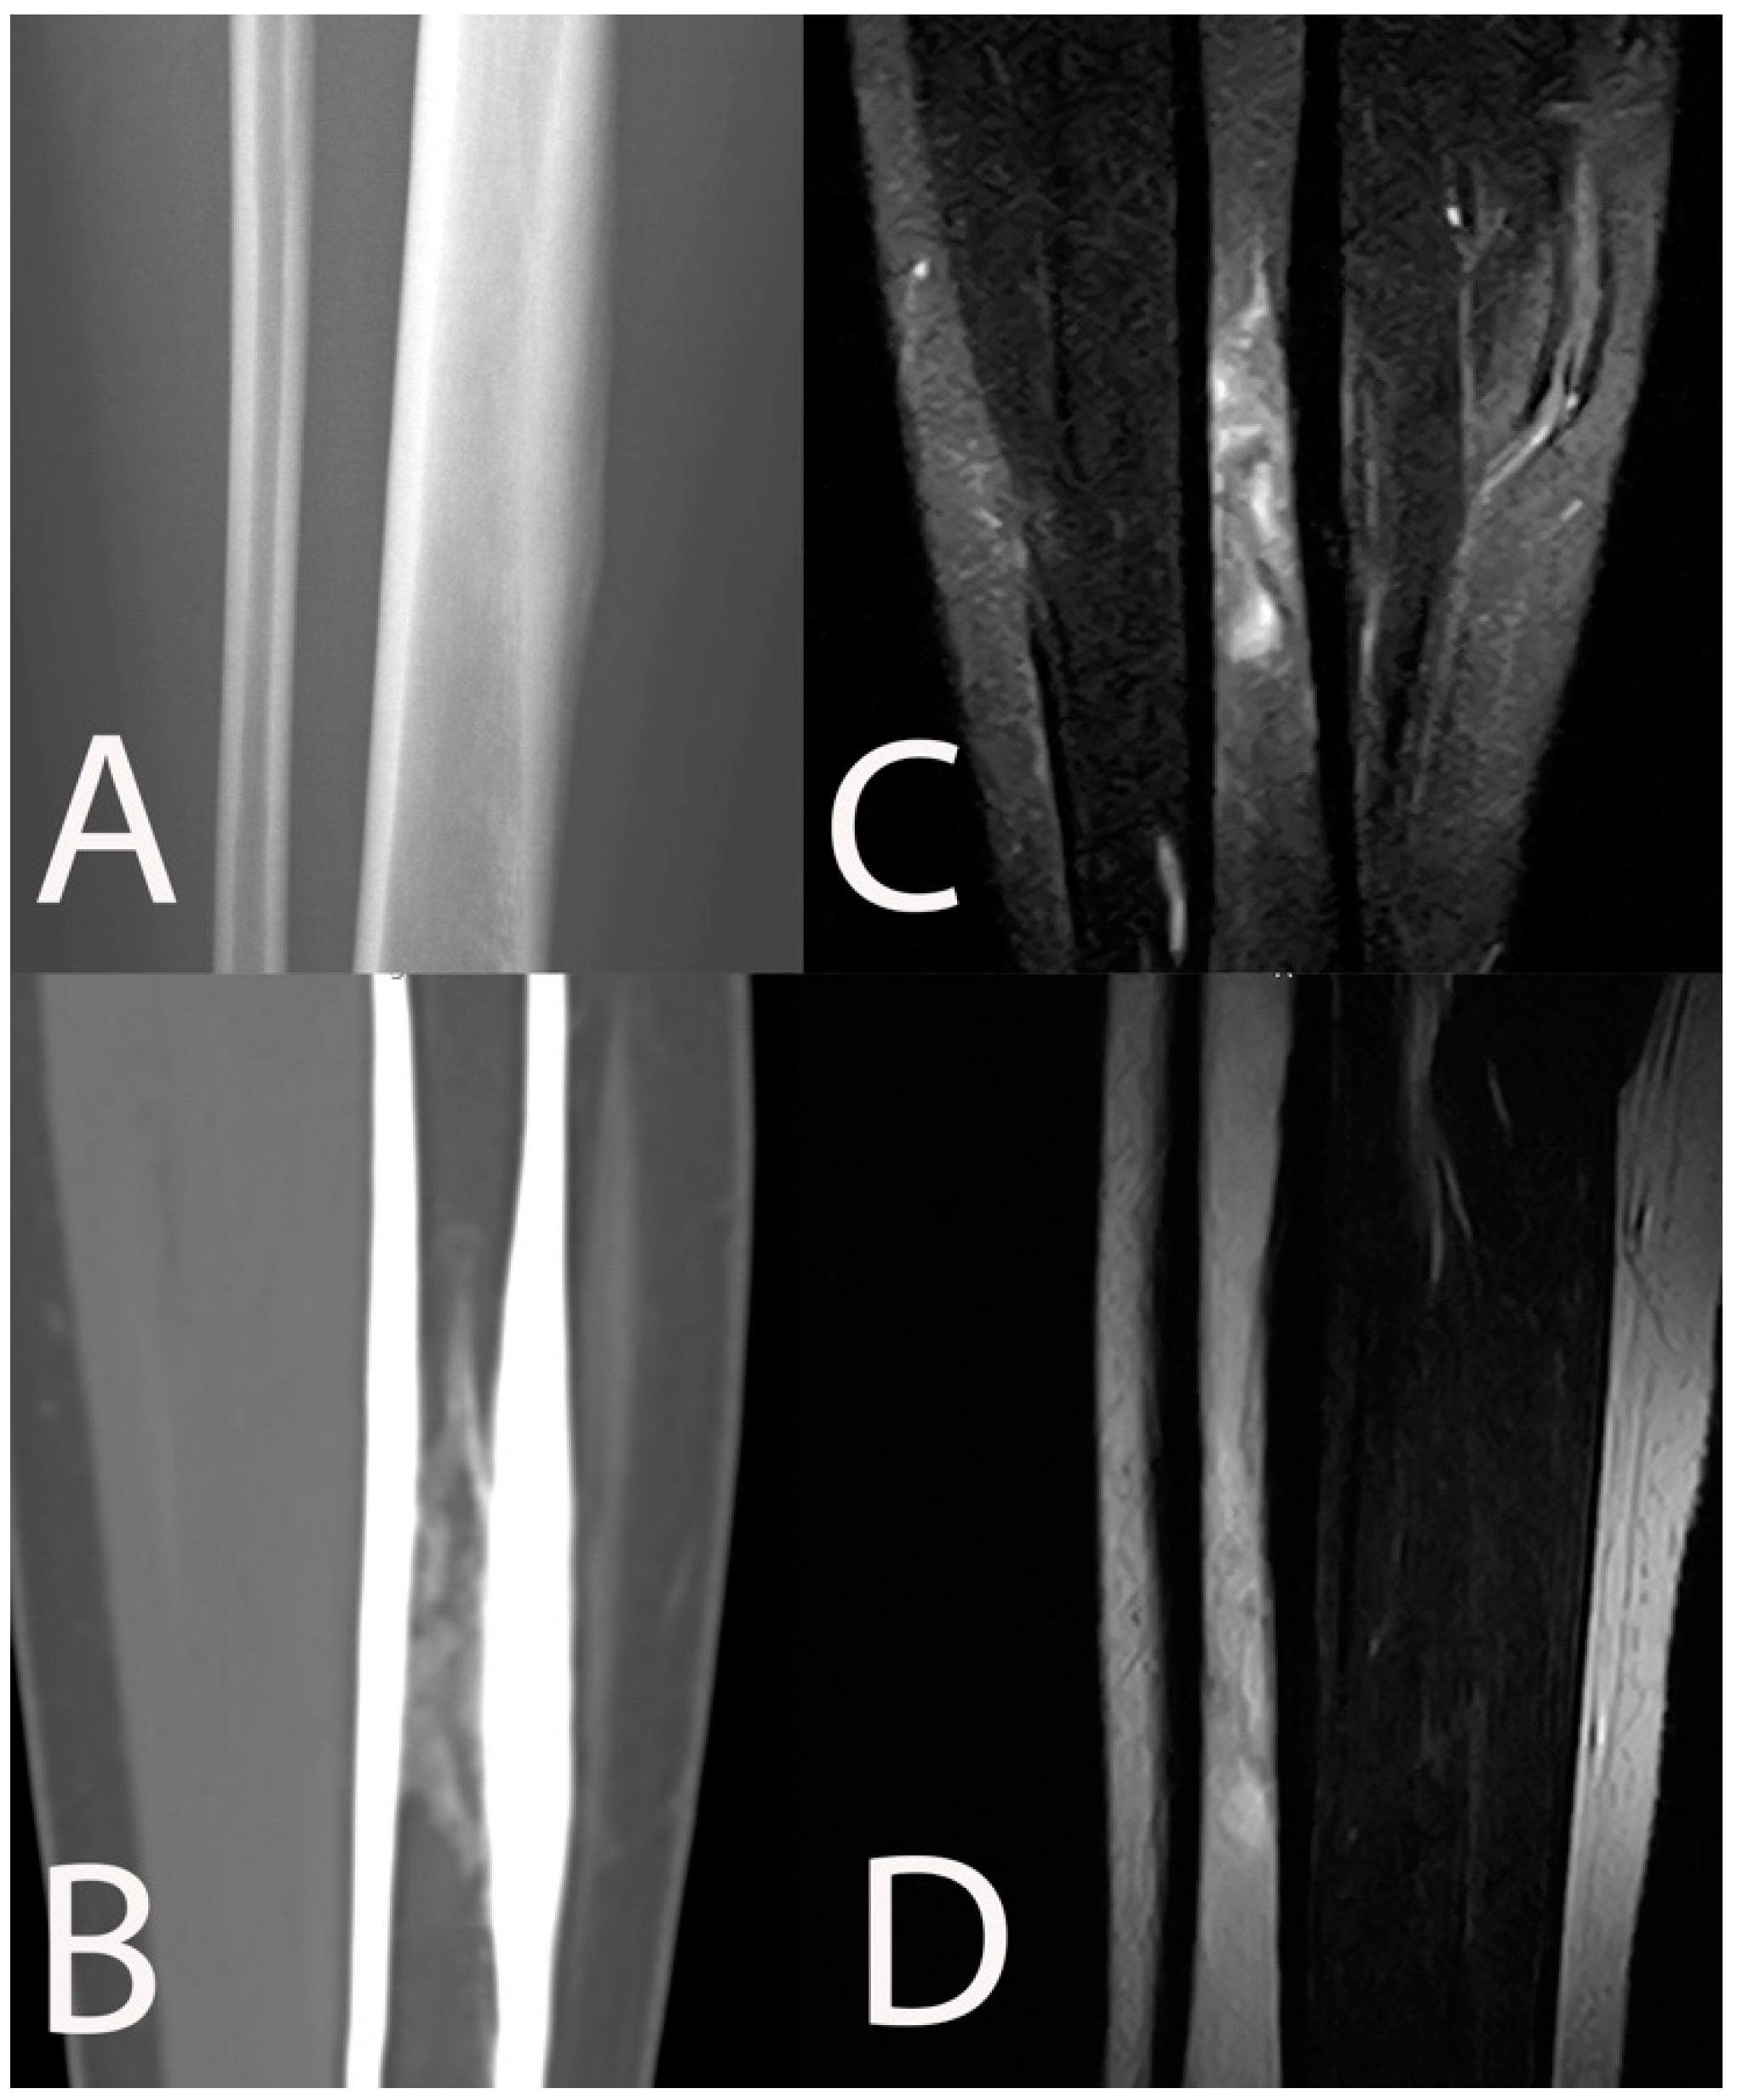

- Metsemakers, W.J.; Morgenstern, M.; McNally, M.A.; Moriarty, T.F.; McFadyen, I.; Scarborough, M.; Athanasou, N.A.; Ochsner, P.E.; Kuehl, R.; Raschke, M.; et al. Fracture-related infection: A consensus on definition from an international expert group. Injury 2018, 49, 505–510. [Google Scholar] [CrossRef] [PubMed] [Green Version]

- McNally, M.; Govaert, G.; Dudareva, M.; Morgenstern, M.; Metsemakers, W.J. Definition and diagnosis of fracture-related infection. EFORT Open Rev. 2020, 5, 614–619. [Google Scholar] [CrossRef] [PubMed]

- Lee, Y.J.; Sadigh, S.; Mankad, K.; Kapse, N.; Rajeswaran, G. The imaging of osteomyelitis. Quant. Imaging Med. Surg. 2016, 6, 184–198. [Google Scholar] [CrossRef] [Green Version]

- Bühne, K.H.; Bohndorf, K. Imaging of posttraumatic osteomyelitis. Semin. Musculoskelet. Radiol. 2004, 8, 199–204. [Google Scholar] [CrossRef] [PubMed]

- Govaert, G.A.; IJpma, F.F.; McNally, M.; McNally, E.; Reininga, I.H.; Glaudemans, A.W. Accuracy of diagnostic imaging modalities for peripheral post-traumatic osteomyelitis–a systematic review of the recent literature. Eur. J. Nucl. Med. Mol. Imaging 2017, 44, 1393–1407. [Google Scholar] [CrossRef] [PubMed] [Green Version]